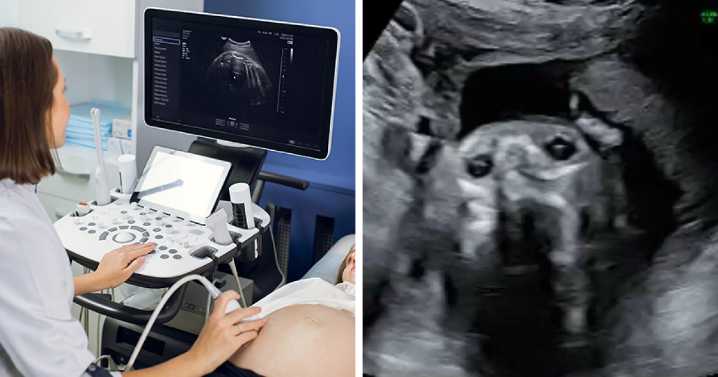

Inês Egner, an influencer and soon-to-be mother from Portugal, couldn’t believe her eyes when her 20-week anatomy scan revealed something unexpected, and hilarious.

Instead of her baby, the machine showed what appeared to be the face of her dog, Goulash, staring back at her.

The video, uploaded to TikTok on October 9, 2025, has now been viewed over 3 million times, with commenters both laughing and agreeing that the resemblance between her unborn son and her five-year-old dog was impossible to unsee.

“We were so excited for our anatomy scan,” Egner wrote across the first slide of her post. “Only to get our photos back and realise our son looks remarkably like our dog!”